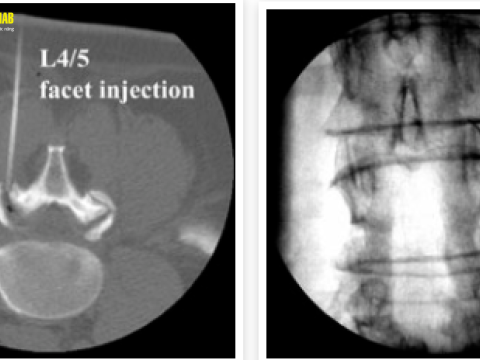

Tiêm cột sống